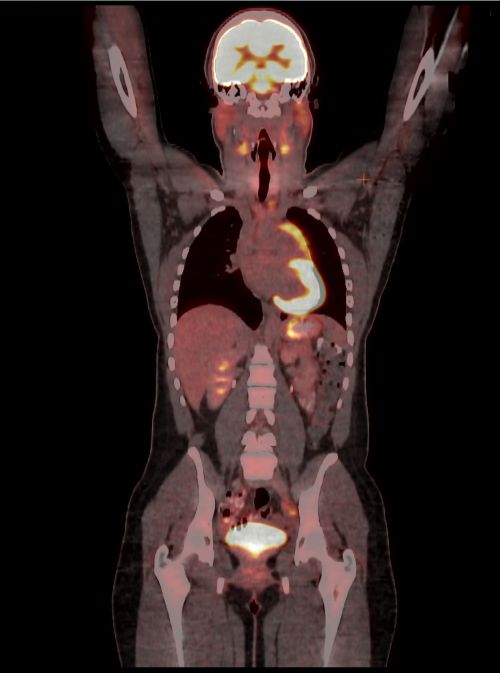

What Does A Pet Scan Show About Lung Cancer - Cancer News ... from popcultureworldnews.com A cancer man in love will sometimes act in strange ways when around the woman he cares for. On a horoscope wheel, the fourth house is located at the very bottom, representing the foundation of the chart. They need someone who is okay with receiving gifts and constant attention. Less likely than other signs to bail when the going gets rough, cancers are very loyal and determined to work things out. But, cancer men in love will eventually begin opening up to their significant others. A cancer understands that a taurus needs. A cancer will show they care by spending time with your family. While a taurus likes to be catered to, a cancer are more than happy to do the catering when in love.